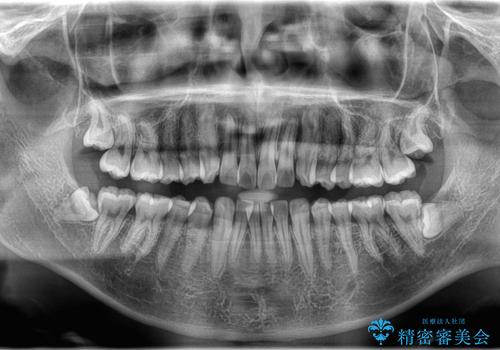

- 歯のデコボコが気になるを主訴に来院された患者様です。

インビザラインで歯は抜かずに非抜歯でデコボコを改善しました。

インビザラインで叢生の改善を行いました。

歯は抜かずに、拡大と少しのIPRで並べました。